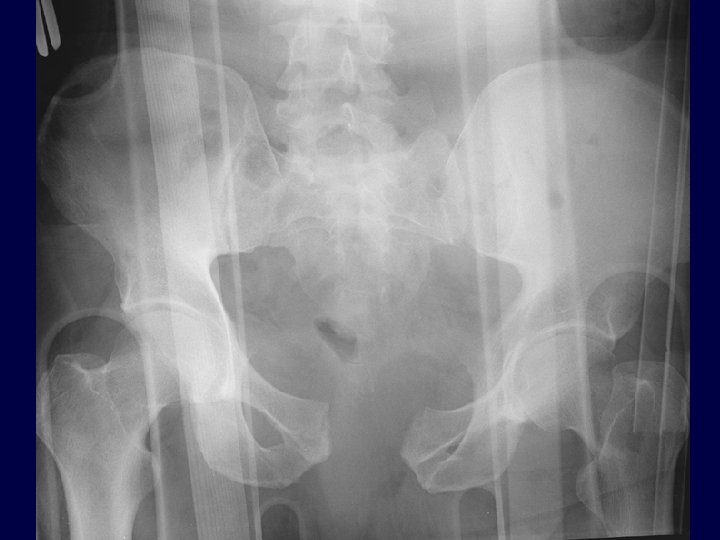

Pelvic Ring Injuries High energy Morbidity/Mortality Hemorrhage

Pelvic Ring Injuries An unstable pelvic injury may allow hemorrhage to collect in the true pelvis as there is no longer a constraint which allows tamponade. The volume was traditionally assume to be a cylinder with a volume of 4/3π r 3, However… Best estimated by a hemi-elliptical sphere (Stover et al, J Trauma, 2006)

Pelvic Fractures & Hemorrhage • Fracture pattern associated with risk of vascular injury (Young & Burgess) • External rotation and vertical shear injury patterns at higher risk for a vascular injury that internal rotation patterns • APC & VS (antero-posterior compression and vertical shear) at increased risk of hemorrhage • Injury patterns that are tensile to N-V structures at increased risk • (eg iliac wing fractures with GSN extension Dalal et al, JT, 1989 Burgess et al, JT, 1990 Whitbeck et al, JOT, 1997 Switzer et al, JOT, 2000 Eastridge et al, JT, 2002

Pelvic Fractures & Hemorrhage: Young and Burgess Classification Lateral Compression (LC) Anteroposterior Compression (APC) ER & VS > IR APC & VS at increased risk Vertical Shear (VS)